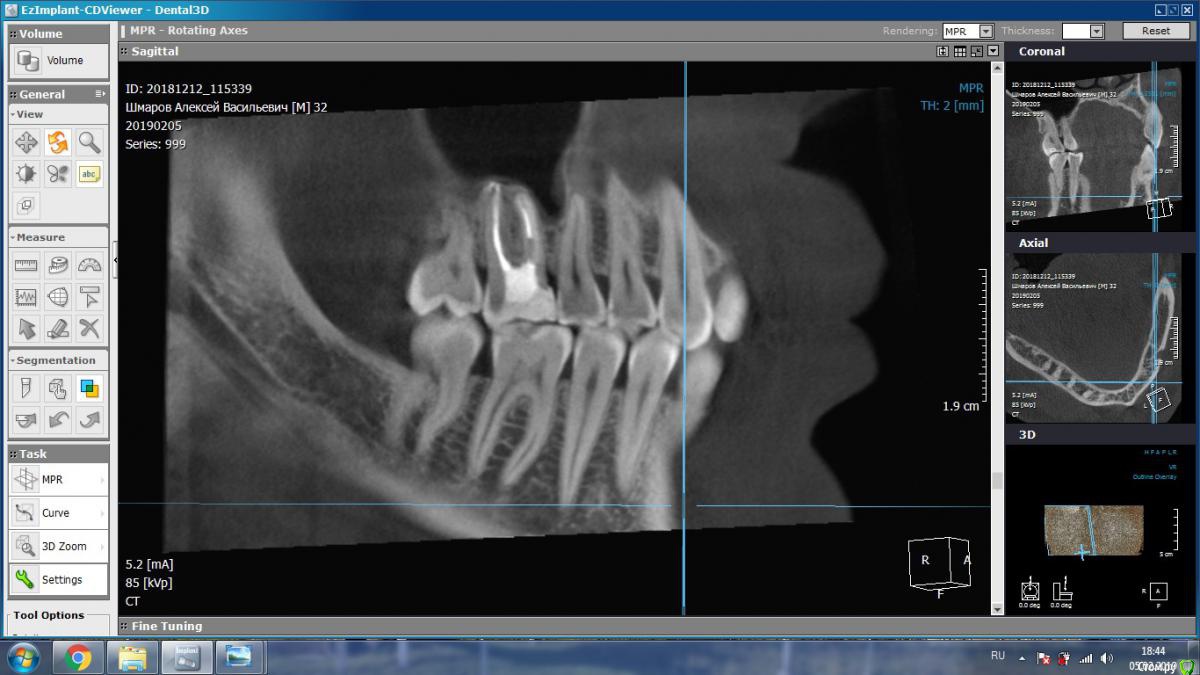

aleks.k Опубликовано 6 февраля, 2019 Автор Поделиться Опубликовано 6 февраля, 2019 Срезы Ссылка на комментарий

aleks.k Опубликовано 6 февраля, 2019 Автор Поделиться Опубликовано 6 февраля, 2019 Еще один срез, может быть более удачный чем первые в этой проекции Ссылка на комментарий

DmitrySH Опубликовано 6 февраля, 2019 Поделиться Опубликовано 6 февраля, 2019 Срезы Очень хорошо. Теперь как первые три, но увеличить 16 зуб. Остальные нам мало интересны, пазуха тоже Ссылка на комментарий

DmitrySH Опубликовано 7 февраля, 2019 Поделиться Опубликовано 7 февраля, 2019 В шестом зубе похоже еще 1 канал есть Ссылка на комментарий

DmitrySH Опубликовано 7 февраля, 2019 Поделиться Опубликовано 7 февраля, 2019 Я так понимаю что меня записали на удаление, по причине того, что стоматолог не обладает квалификацией для такого лечения? Ведь нужен именно эндодантист. Допустим что канал есть. Если его лечить, по цене примерно сколько это стоит? В Калуге думаю нет таких специалистов. Хотя бы примерно. И в случае лечения есть ли гарантия на такой зуб? Еще нужен микроскоп. Потому как если бы канал был хорошо виден, то его бы сразу нашли и обработали. Ссылка на комментарий